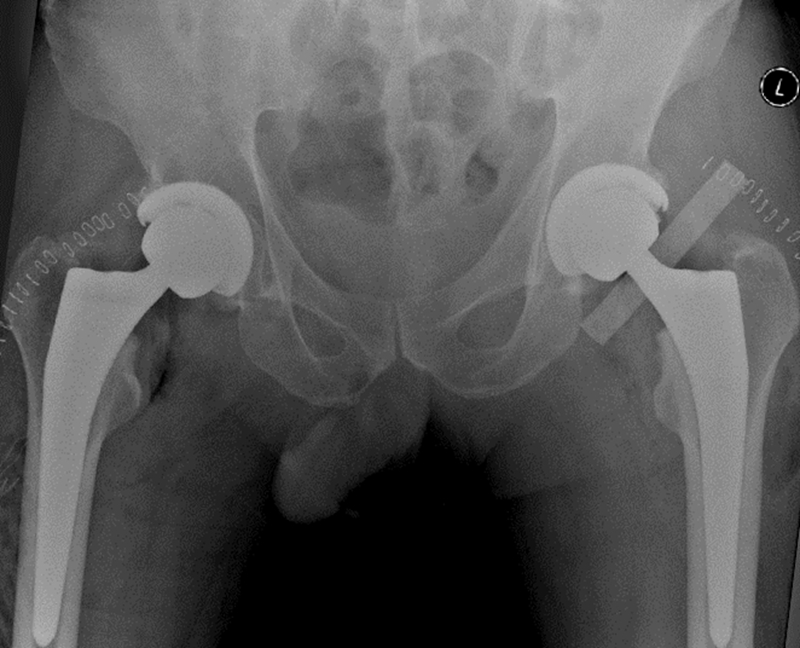

患者男性,48岁,诊断为“股骨头坏死”(图3),接受了VTS导航辅助下初次双侧全髋关节置换术,手术顺利,一侧手术仅用时约60分钟。术后影像学结果显示,假体位置、角度和肢体长度都非常满意(图4),次日患者即可下地活动,术后3日后即平稳出院。

图3 患者术前X光片,48岁男性,双侧股骨头坏死

图4 患者术后X光片,假体位置和角度理想,下肢偏心距和长度得到了重建